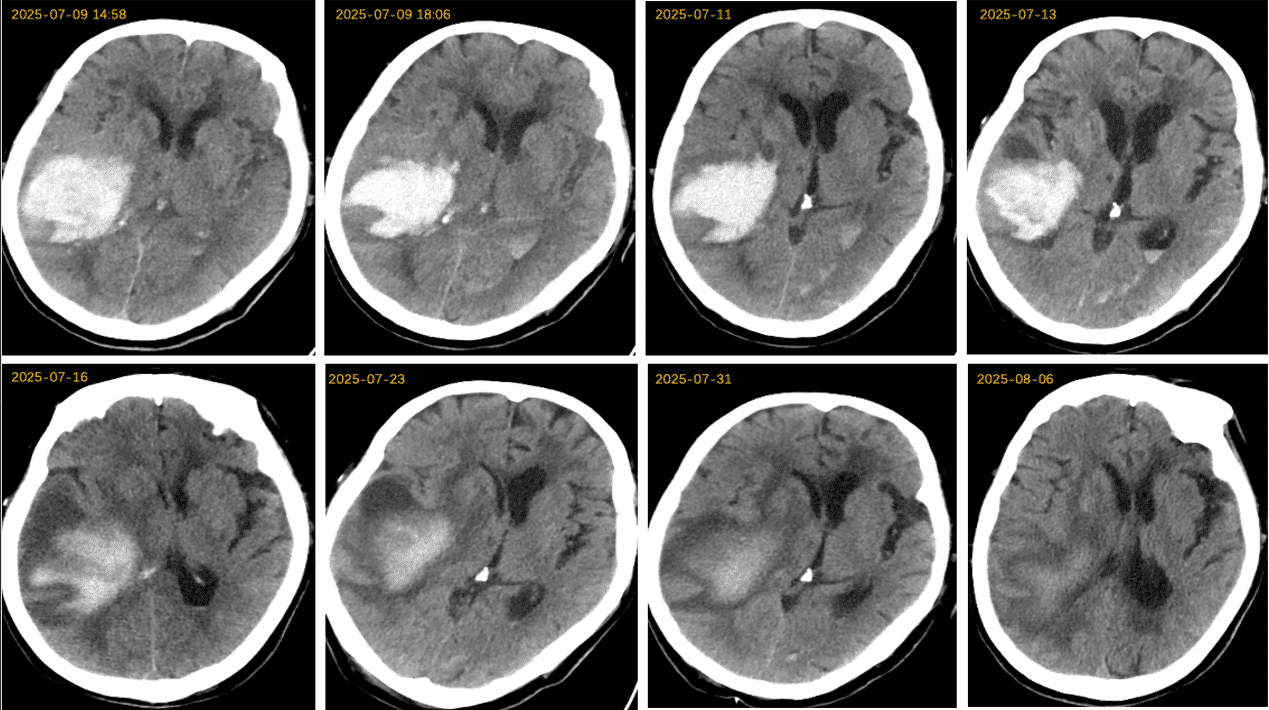

头CT(2025-7-9 13:40 本院)提示右侧颞叶、基底节区、顶叶及额叶高密度影,且破入侧脑室,考虑静脉溶栓后出血转化P2型。

⏰ 基于多田公式,粗测出血量>75ml,联系神经外科,建议手术,鉴于颅内存在动脉瘤,风险极高,家属拒绝手术方案。内科启动甘露醇联合利尿剂脱水、氨甲磺酸止血治疗,积极预防及治疗并发症。

动态观测CT变化,颅内出血及水肿情况经历 起病⇢进展⇢高峰⇢消退 动态变化,患者意识由昏迷逐渐转为嗜睡状态。三、临床诊断